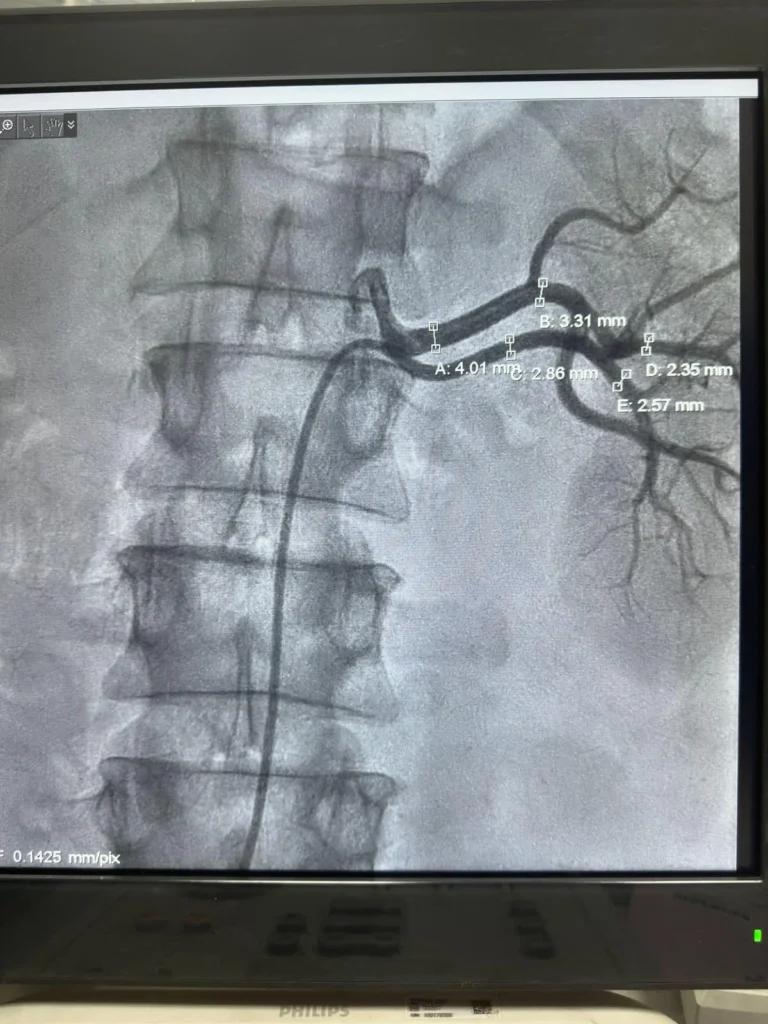

This innovative procedure targets the renal sympathetic nerves, effectively reducing their overactivity, which is a significant contributor to high blood pressure. This procedure involves inserting a catheter through right groin into the renal arteries. Where radiofrequency pulses are used to burn the sympathetic nerves. Which helps reduce high blood pressure in patients who do not respond to common medications.